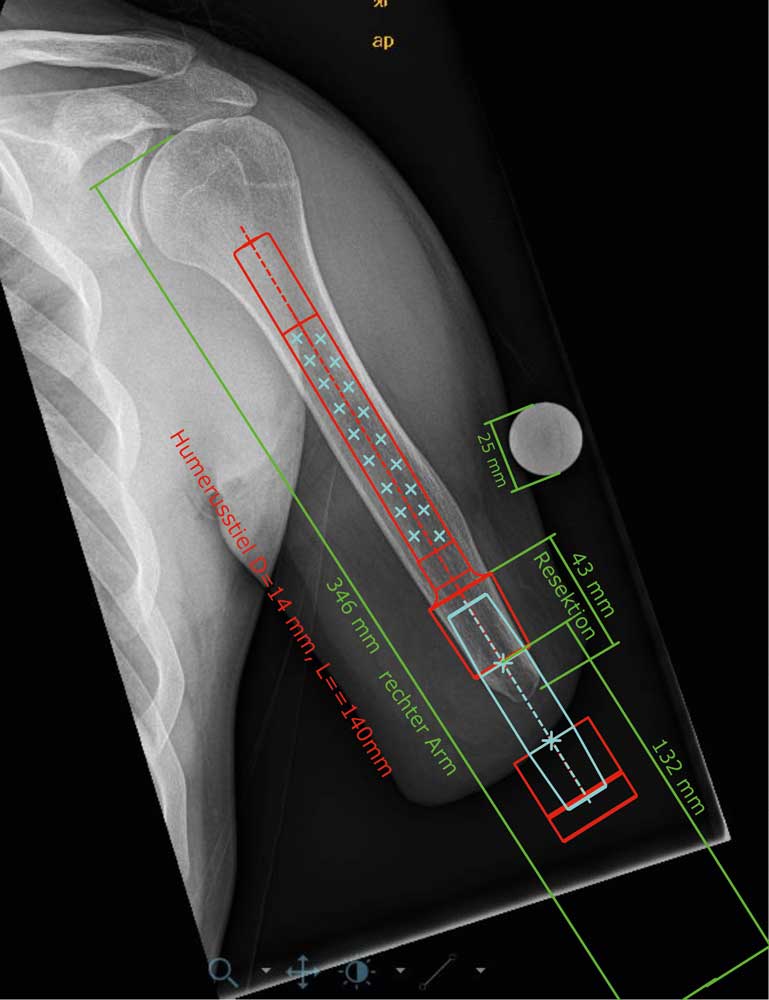

Um Funktionsvergleiche und Prothesennutzung vor und nach der Versorgung zu ermöglichen, werden zudem Daten per Fragebögen erhoben und klinische Testverfahren durchgeführt. Vor der ersten Operation wird zusammen mit dem Orthopädietechniker, dem Operateur und der ESKA Orthopaedic GmbH die Planung für die TOPS an referenzierten Röntgenaufnahmen vorgenommen (Abb. 9). Dabei fließen die Aufbauhöhe der geplanten Passteile, die Implantatgröße und die ossäre Struktur des Implantatlagers in die Planung ein. Anschließend wird bereits Kontakt zum Kostenträger gesucht, um das Vorgehen zu erläutern und Probleme im Versorgungsablauf zu vermeiden. Der weitere Verlauf:

- Im ersten Schritt (“Step 1″) erfolgt die Implantation des Endomoduls. Wichtig dabei ist, dass die Weichteile hinreichend gekürzt werden, um die spätere Stomakanalbildung mit einer Gesamtlänge von max. 20 mm zu erreichen. Daher unterscheidet sich das Vorgehen erheblich von klassischen stumpfkorrigierendenden Operationen. Denn die sonst angestrebte Muskeldeckung des knöchernen Stumpfendes muss zugunsten eines kurzen Stomakanals vermieden werden. Trotzdem muss auf eine balancierte Muskelanheftung am Knochen geachtet werden, um eine adäquate Prothesenführung zu gewährleisten. Der Hautverschluss berücksichtigt bereits die spätere Stomakanalposition (Abb. 10 a–c). Der Patient wird etwa 7 Tage nach der Operation entlassen. Es schließt sich eine ambulante Physiotherapie zur allgemeinen Konstitutionsverbesserung und Kontrakturbehandlung der proximalen Gelenke an. Weitere klassische physiotherapeutische Nachbehandlungen analog zu einem Amputationsstumpf werden aufgrund der Methodik der TOPS nicht durchgeführt.